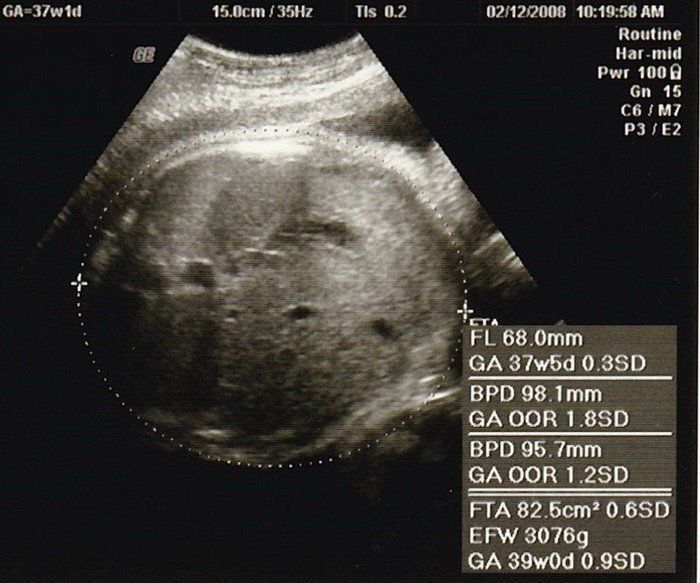

Amiさんの妊娠37週目のエコー写真

正期産に入りました。常に大きめと言われていた我が子は遂に3000g超え! またも頭部と大腿骨しか写っていません。大きめ我が子にはスルッと生まれてほしくて、毎日毎日お散歩していました。